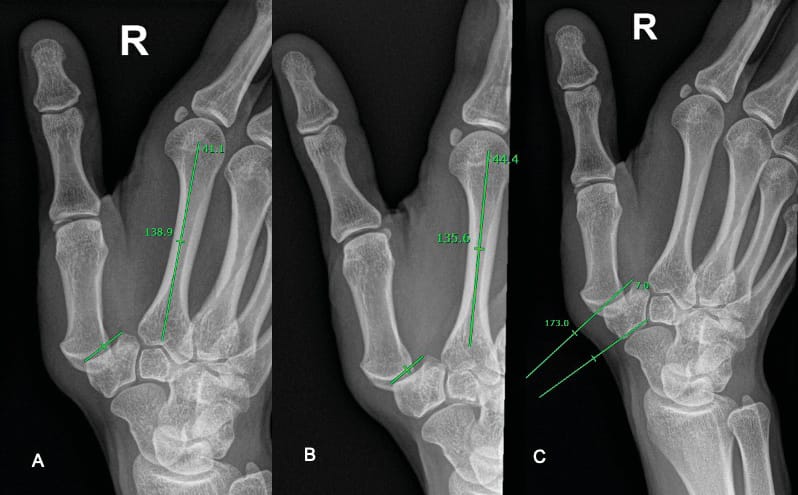

When a young patient presents with pain at the thumb base, we can expect concern over instability due to laxity or often further to dysplasia. This can be measured by using either the trapezial tilt (Dévers angle) as described by Kapandji and Heim [13] Taleisnik J. The Wrist, 1st edn. New York, Churchill Livingstone, 1985: 95–96. , or the trapezial inclination, more recently described by Van Royen [15] Van royen K, Gevers M, Vanmierlo B, Scheerlinck T, Goubau J. Radiological Measurment of trapezial Dysplasia – Variation of trapezial tilt and trapezial inclination. Hand Surg Rehab. 40 (2021) 44-50. The trapezial tilt is measured from the distal joint surface of the trapezium on a Kapandji frontal view and the axis of the second metacarpal. It measures 129° +/- 6° on average. The trapezial inclination, which its authors believe to be more consistent [15] Van royen K, Gevers M, Vanmierlo B, Scheerlinck T, Goubau J. Radiological Measurment of trapezial Dysplasia – Variation of trapezial tilt and trapezial inclination. Hand Surg Rehab. 40 (2021) 44-50, is measured between the proximal articular surface of the trapezium (PAST) and the distal articular surface of the trapezium (DAST). It measures 10° +/- 5° on average. The inconsistency of the trapezial tilt is illustrated in figure 9. This can be explained by the ‘cantilever’ bending of the trapezium, as described by Van Royen et al. [15] Van royen K, Gevers M, Vanmierlo B, Scheerlinck T, Goubau J. Radiological Measurment of trapezial Dysplasia – Variation of trapezial tilt and trapezial inclination. Hand Surg Rehab. 40 (2021) 44-50.